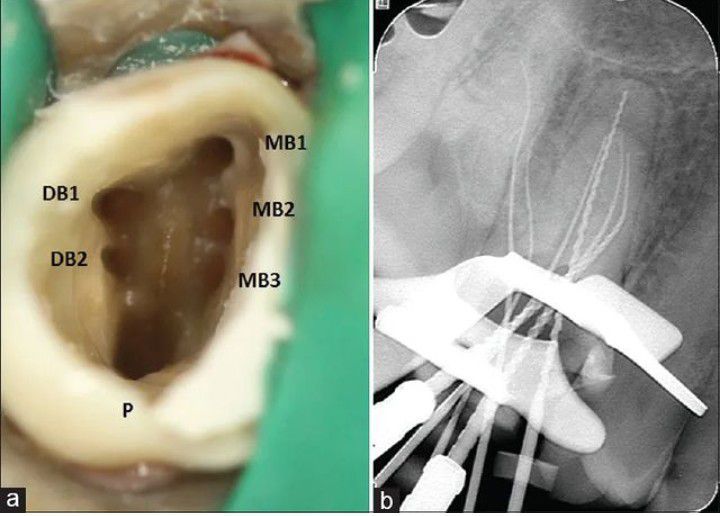

Molar with Six Roots

Here is a molar with six roots during a doot canal procedure.